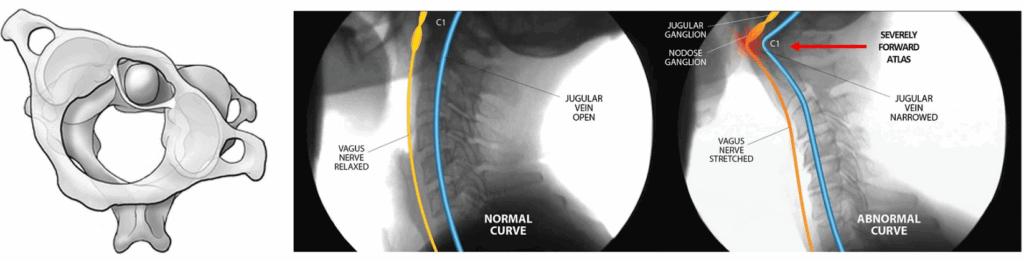

미주신경은 뇌신경의 하나이자 자율신경계의 부교감신경으로서 우리 몸에서 매우 중요한 신경입니다. 미주신경은 가장 길고 넓게 퍼져 있는 신경인데 목 부위에서는 경추 양옆에서 가로돌기의 앞에 가깝게 놓여있기 때문에 상부경추의 부정렬로 인한 압박, 스트레칭, 당기는 힘에 취약합니다.

두개골로 들어가고 나오는 혈관(내경정맥, 내경동맥)과 뇌신경 XI, XII, X, IX (미주신경, 부신경, 설학신경, 혀인두신경) 등이 목혈관신경집이라는 근막으로 둘러싸여 있습니다. 목혈관신경집은 아틀라스(Atlas)라는 경추1번 C1의 가로돌기(transverse process)와 측두골의 경상돌기(styloid process), 상인두수축근(superior contrictor) 사이 공간에 있고, 상부경추 C1(Atlas)과 C2(Axis)가 이탈되면 기계적 힘을 받거나 압박될 수 있습니다.